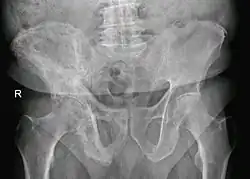

The exact cause is unknown, although leading theories indicate both genetic and acquired factors (see Causes). Paget's disease may affect any one or several bones of the body (most commonly pelvis, tibia, femur, lumbar vertebrae, and skull), but never the entire skeleton,[1][2][3] and does not spread from bone to bone.[4] Rarely, a bone affected by Paget's disease can transform into a malignant bone cancer.